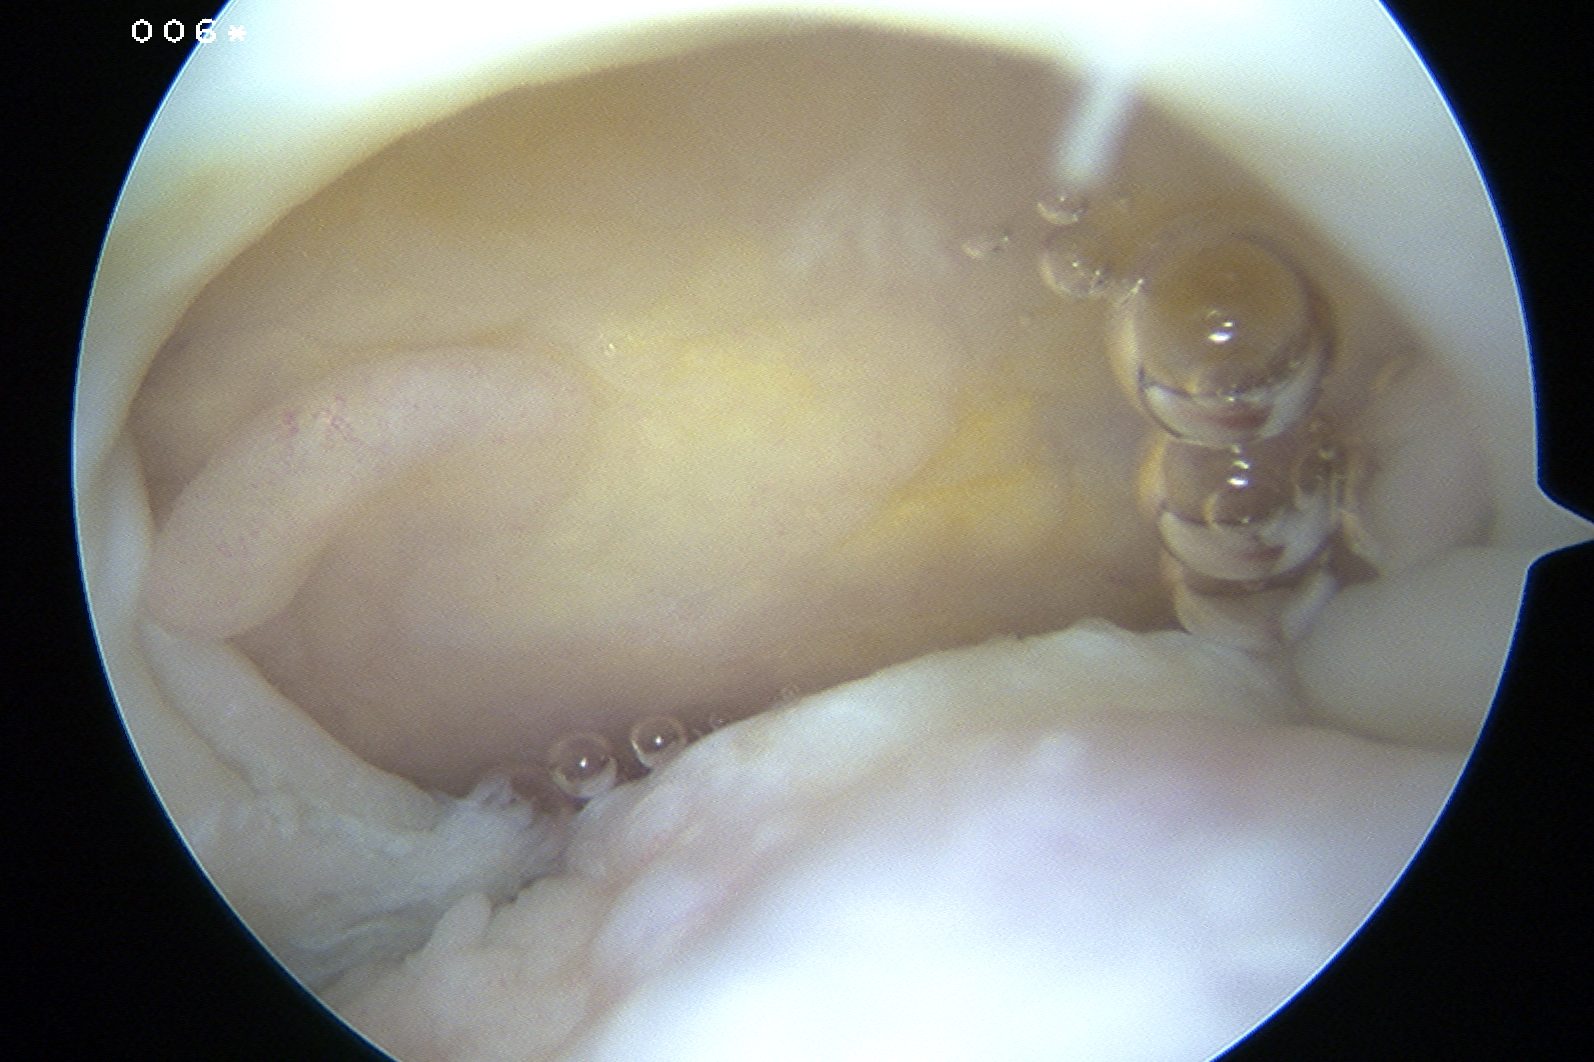

Arthroscopy

Tear patterns of supraspinatus and infraspinatus

| Crescent shaped | U shaped | L Shaped |

|---|---|---|

|

Small to medium tears Repair to footprint |

Large tears Need margin convergence then repair to footprint |

Antero-superior or postero-superior tears Need to mobilize cuff anterior or posterior |

|

|

|

Crescent, U shaped and massive rotator cuff tears